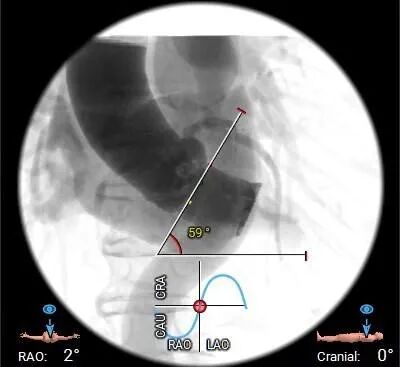

• 主动脉瓣水平夹角约59°,接近横位心,主动脉弓宽度角度可,弓顶部少许钙化分布;

• 接近横位心,升主无扩张,主动脉弓宽度角度可,预估TaurusElite输送器可顺利过弓及跨瓣,弓顶部少许钙化分布,过弓时轻柔操作;